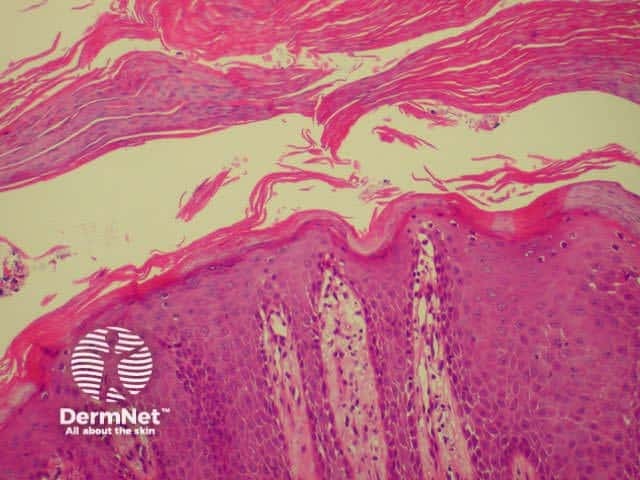

Histology of psoriasis is characterised by parakeratosis (cell nuclei within stratum corneum) and thickened projections of the prickle cell layer of keratinocytes (psoriasiform hyperplasia). There is no granular layer. Polymorphonuclear leukocytes and lymphocytes infiltrate dermis (CD8+) and epidermis (CD4+).

Thick stratum corneum and projections of epidermis Note inflammatory infiltrate Parakeratosis (cell nuclei within thickened stratum corneum)